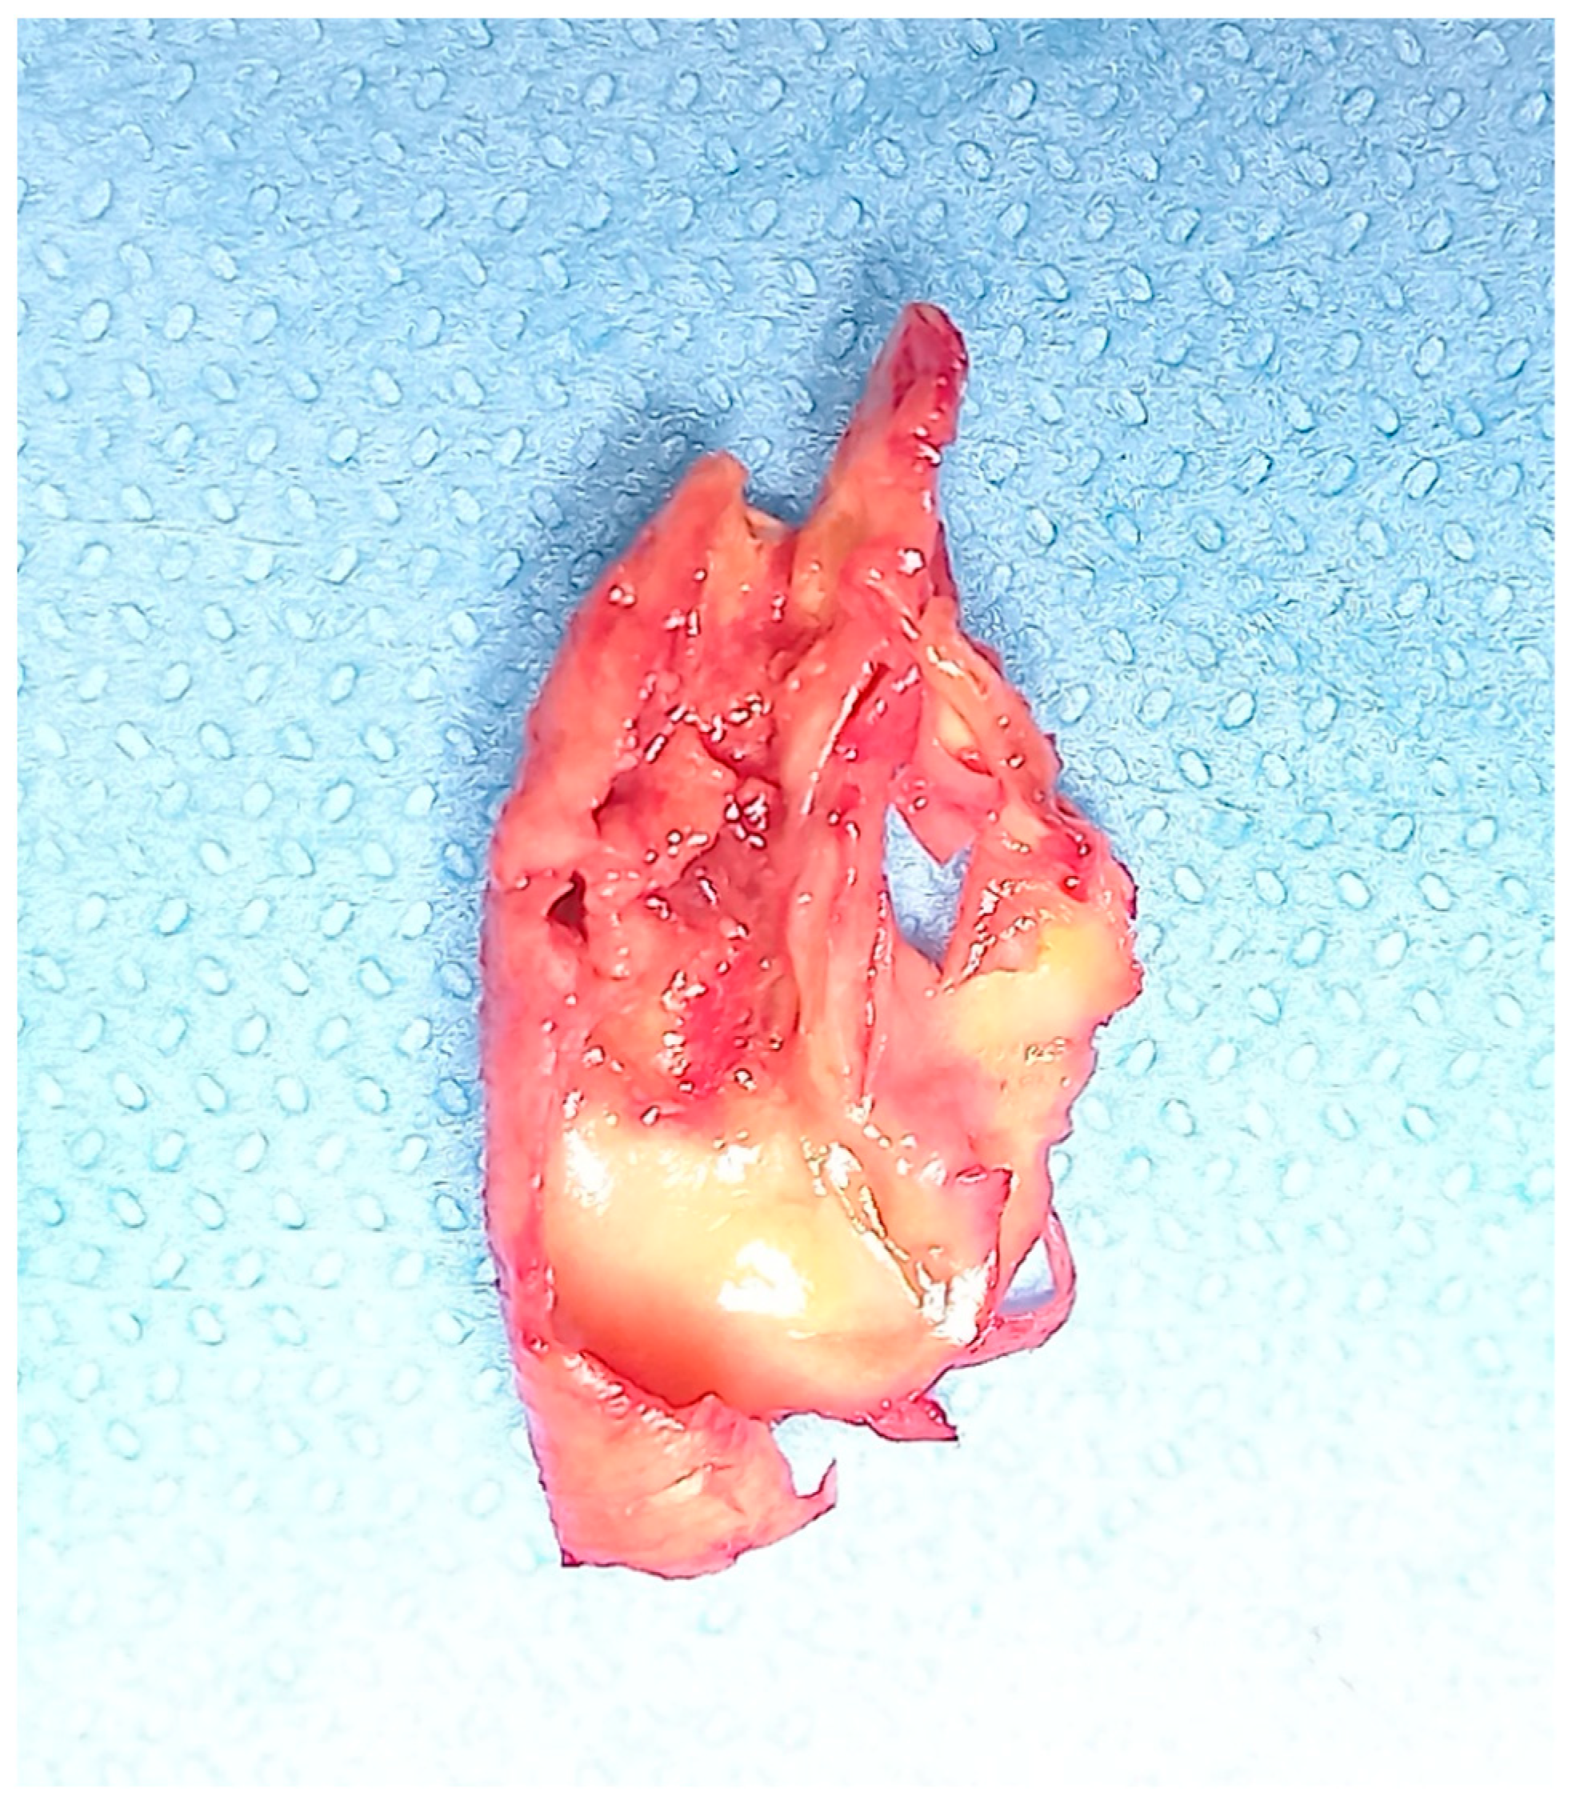

Figure 2.

Ulcerated carotid plaque after endarterectomy.